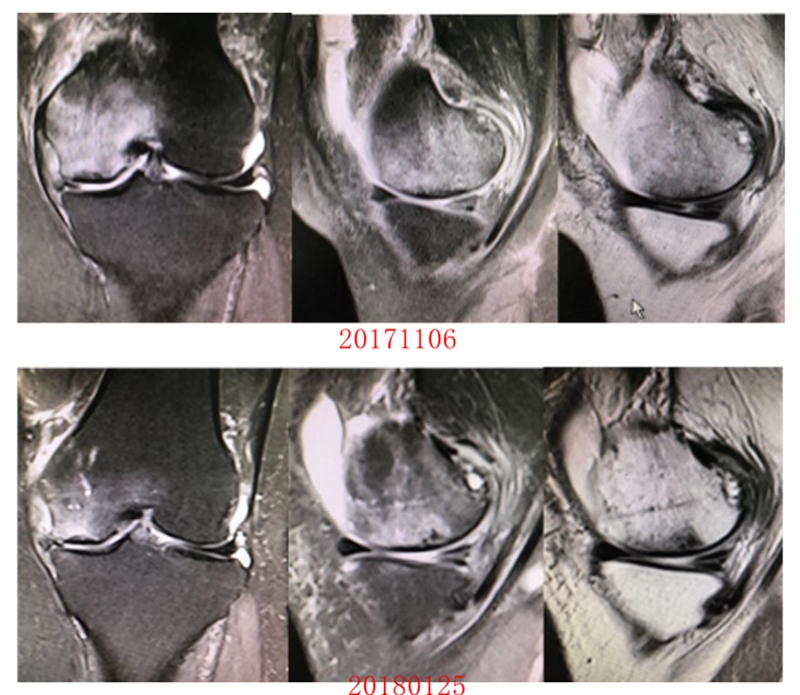

病例:女,65岁,主诉左膝关节内侧疼痛2月余。2017年11月X光未见左膝骨质异常。MR见股骨内侧髁骨坏死,半月板相对突出百分比(RPE)28.3%,合并内侧半月板后根部撕裂,矢状位病变区域前后径为11.67mm,关节线会聚角2.68°

予消炎止痛药物口服、静滴唑来膦酸钠注射液,避免负重6周,后改部分负重,12周后全负重。

2018年2月复查MR见骨髓水肿明显吸收,坏死灶边界清晰,半月板相对突出百分比(RPE)28.92%

2018年6月复查MR见骨髓水肿基本完全吸收,坏死区修复良好,半月板相对突出百分比(RPE)38.54%,患者临床症状消失。

提示坏死好转了,但半月板突出进展了,膝关节的退变加重了。